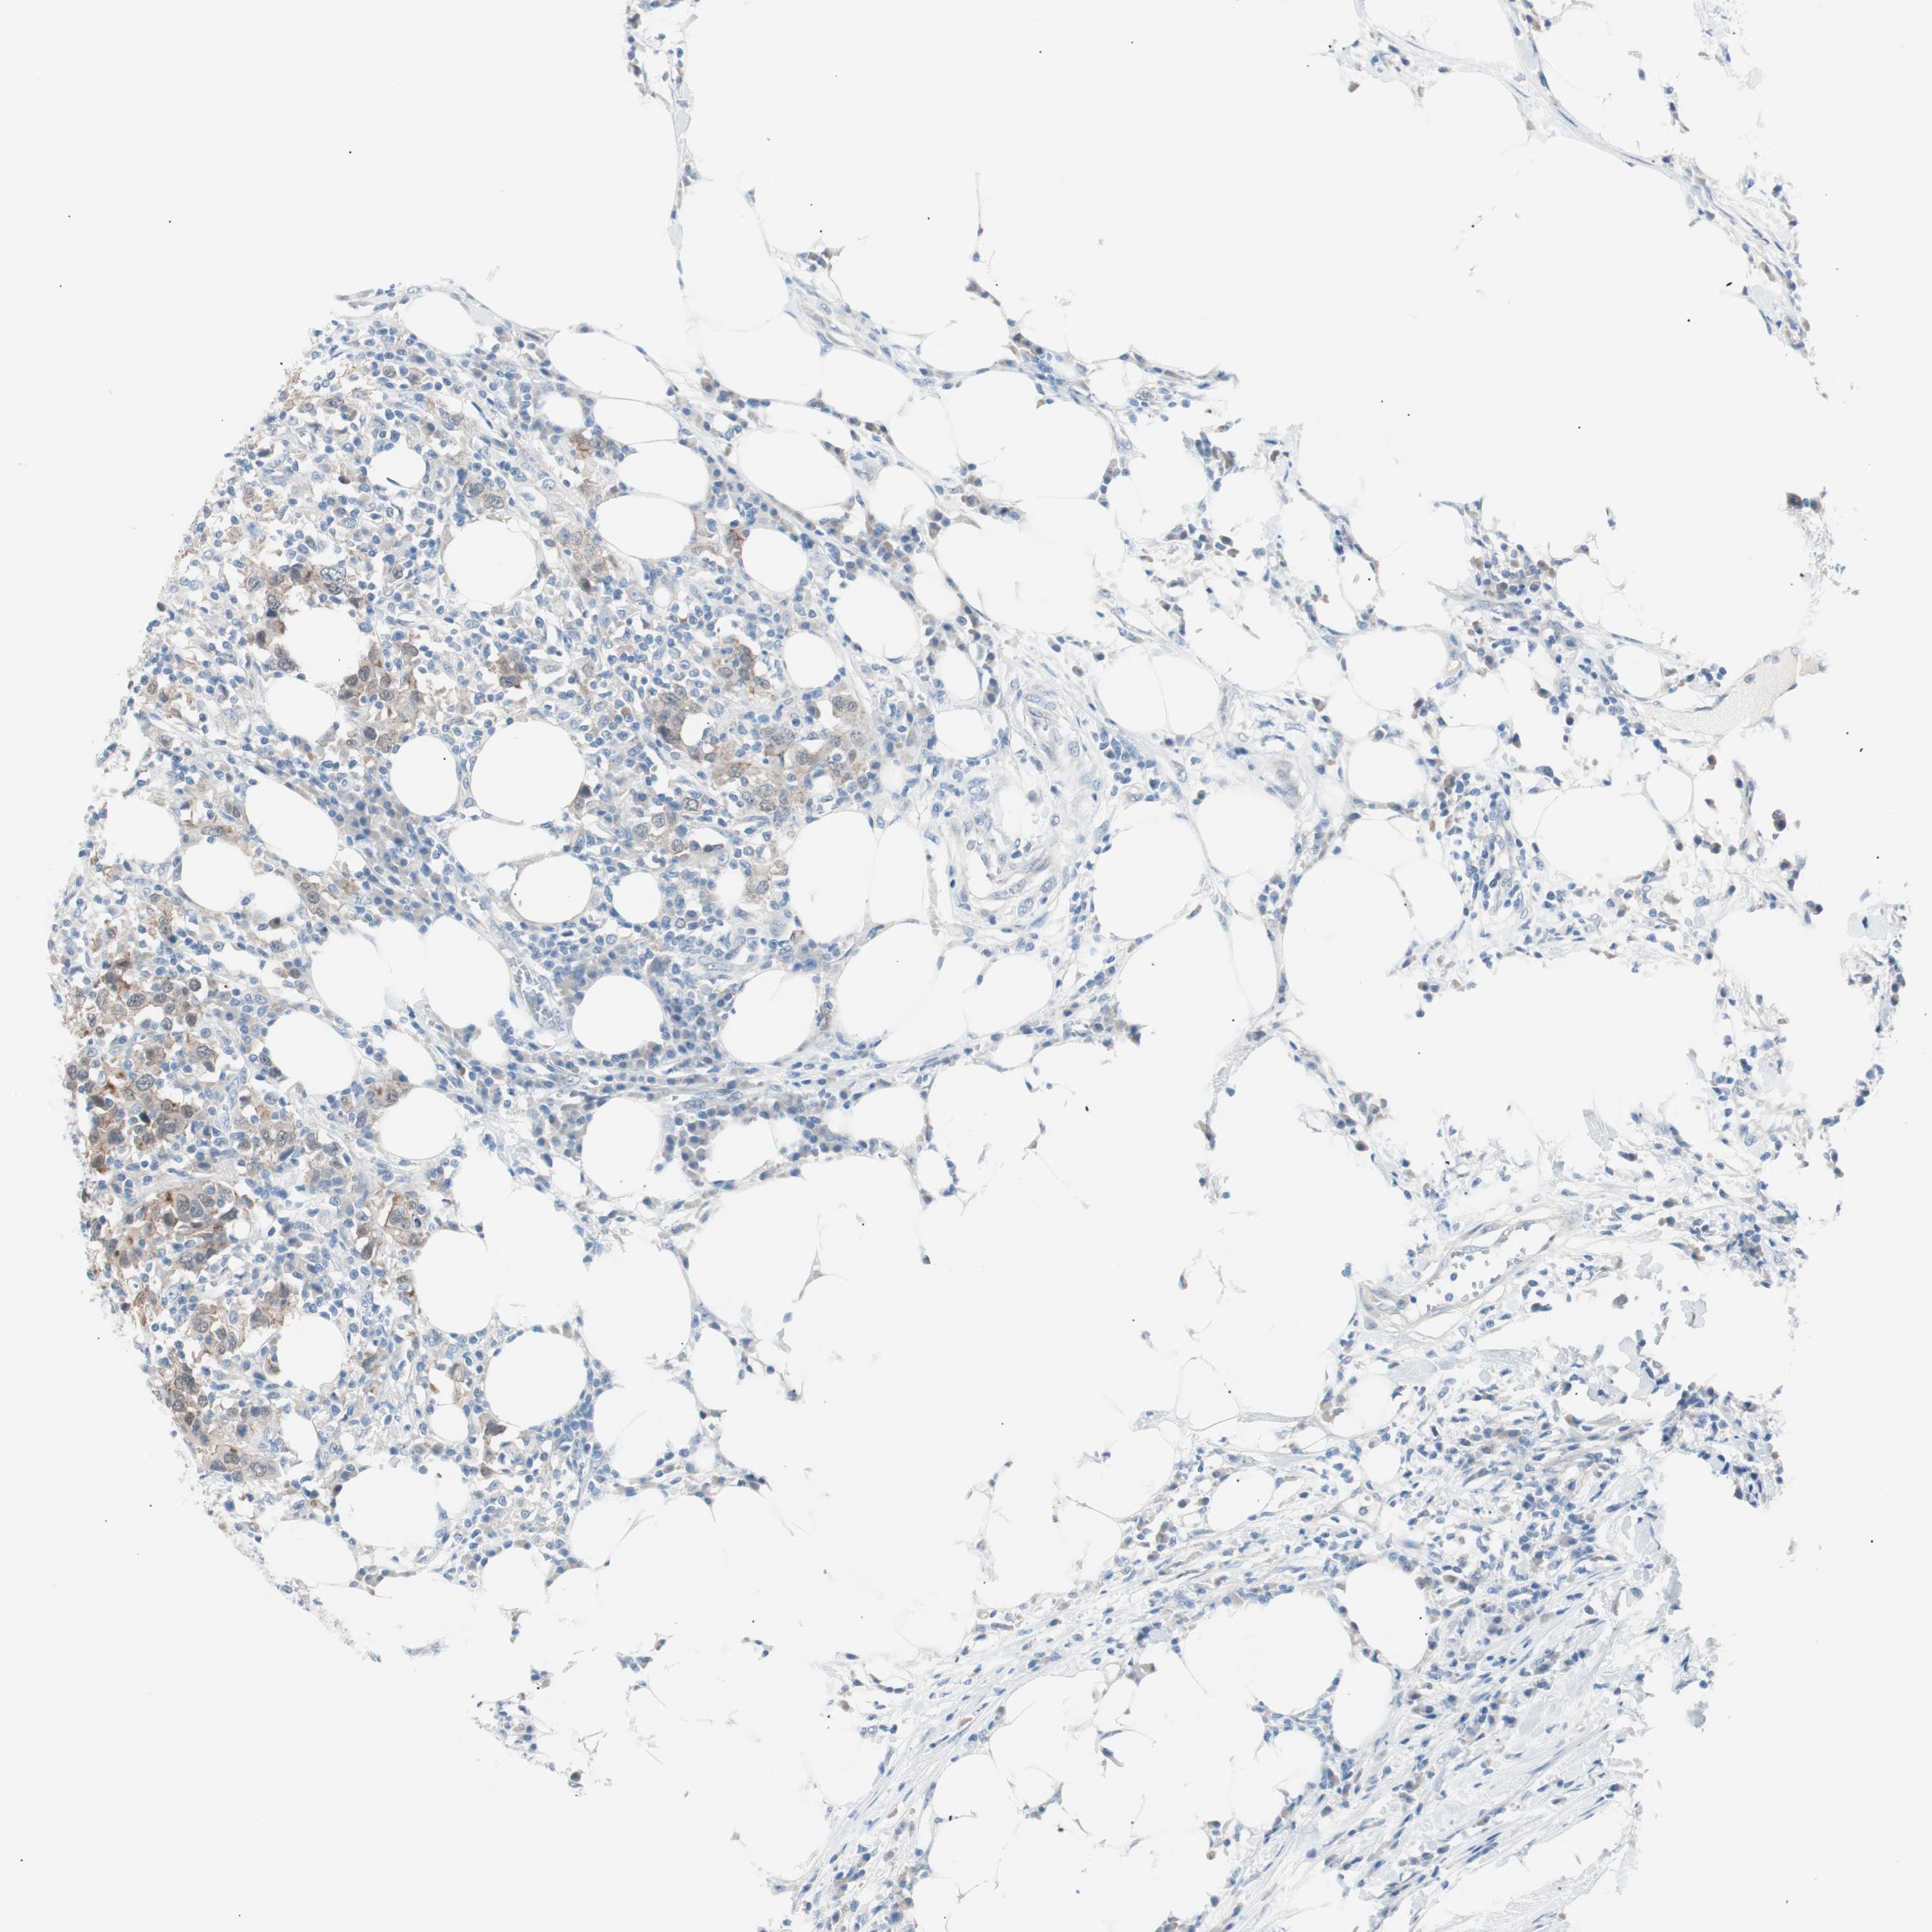

UROTHELIAL CANCER - Protein expressioni

A mouse-over function shows sample information and annotation data. Click on an image to view it in a full screen mode. Samples can be filtered based on level of antibody staining by selecting one or several of the following categories: high, medium, low and not detected. The assay and annotation is described here.

Note that samples used for immunohistochemistry by the Human Protein Atlas do not correspond to samples in the TCGA dataset.

Antibody stainingi

Antibody staining in the annotated cell types in the current human tissue is reported as not detected, low, medium, or high, based on conventional immunohistochemistry profiling in selected tissues. This score is based on the combination of the staining intensity and fraction of stained cells.

Each image is clickable and will lead to virtual microscopy that enables deeper exploration of all samples and also displays staining intensity scores, fraction scores and subcellular localization as well as patient and tissue information for each sample.

Antibody HPA006884

Antibody HPA006885

Antibody CAB002452

Staining

High

Medium

Low

Not detected

Intensity

Strong

Moderate

Weak

Negative

Quantity

>75%

75%-25%

<25%

None

Location

Nuclear

Cytoplasmic/membranous

Cytoplasmic/membranous,nuclear

Urothelial carcinoma, Low grade

Urothelial carcinoma, High grade

Adenocarcinoma, NOS